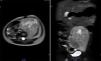

Se realizó la resonancia magnética nuclear (RMN) de abdomen contrastada previa a la resección tumoral, que mostró que la masa envolvía la arteria y vena iliaca izquierdas (fig. 1).

Resonancia magnética de abdomen con contraste que muestra masa sólida de 107×80×76mm de diámetros craneocaudal, anteroposterior y transverso que ocupa hipogastrio, fosa iliaca y flanco izquierdos y gran parte del mesogastrio, pediculada desde los agujeros de conjunción L4-L5, L5-S1 y S1 izquierdos. Sólida, heterogénea, con necrosis, vascularizada, que envuelve parcialmente la bifurcación aórtica y totalmente la arteria iliaca primitiva izquierda y sus ramificaciones, al igual que la vena iliaca.